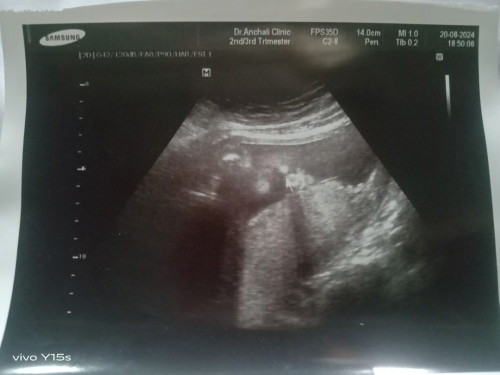

ภาพอัลตร้าซาวด์

แม่ๆช่วยดูหน่อยค่ะ น้องมีปากแหว่งเพดานโหว่มั้ยค่ะ